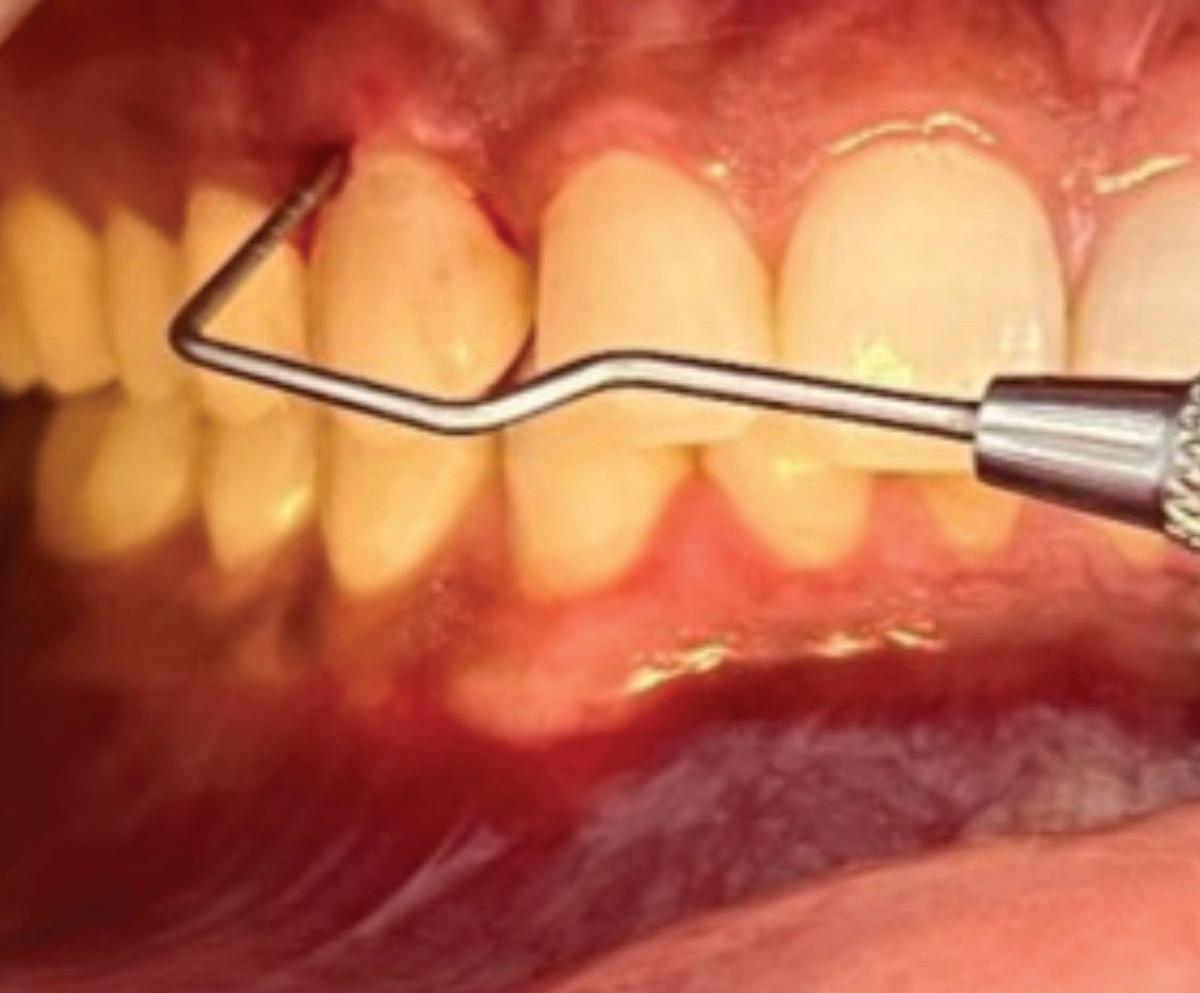

Implications of a persistent CAIPP defect

A CAIPP defect can be expected to accompany the radicular crack or eventually develop. These bony dehiscences are not easily accessible and are not predictably amenable to current periodontal therapies because bacteria reside within the crack and not on the root surface. These defects are often missed by traditional radiography and probing due to their narrow width and interproximal location.

These CAIPP lesions are best identified and monitored with high-resolution CBCT scans (Fig 5). However, even advanced CBCT systems, with voxel sizes as small as 0.075 mm, are not capable of reliably detecting cracks, which are typically much narrower.45 Therefore, the presence of a CAIPP defect, combined with careful clinical diagnostics and evaluation, remains the most reliable indirect indicator of a crack with radicular extension.

The presumed clinical significance of a lingering CAIPP defect is that the persistent biofilm in the crack can lead to further periodontal breakdown and symptoms. However, the changes in these areas were monitored over the course of

previous studies, and these bony lesions did not progress over time and remained asymptomatic.4,26 Together, these studies demonstrated that the persistent bony defect adjacent to the cracks may remain stable and asymptomatic over time, making saving teeth with this technique a realistic option for patients.

Fig 5. CBCT images of a crack-associated isolated periodontal pocketing defect associated with a distal crack in the mandibular right first molar. A. Sagittal view showing angular crestal bone loss (arrow) along a distal radicular crack at the cervical margin. B. CBCT 3-dimensional rendering showing the defect (arrow) at the distal root. C. Axial view showing the defect (arrow) at the distal root.